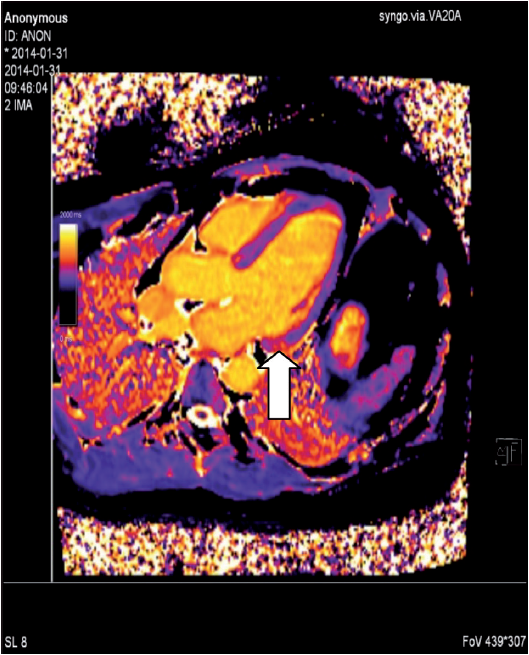

Magnetresonans-teknikken har vist seg å være meget verdifull i diagnostikken av hjertesarkoidose. Metoden innebærer ingen strålebelastning for pasienten, den er ikke invasiv, og gir meget valide data for volum og funksjon av henholdsvis venstre og høyre ventrikkel. Introduksjonen av det ekstracellulære kontrastmiddelet gadolinium har revolusjonert de diagnostiske mulighetene med MR. LGE (late gadolinium enhancement) brukes nå alltid ved utredning av suspekt hjertesarkoidose. Metoden kan avsløre fibrotiske og aktive inflammatoriske forandringer, som ofte finnes i venstre ventrikkelseptum og lateralveggen, og også differensiere mellom dem. Nå for tiden brukes også ulike mapping-teknikker for å finne tilsvarende funn. Forandringene er likevel ikke helt spesifikke for hjertesarkoidose, men man tolker LGE- mønster ut fra lokalisasjon og utbredning i ventrikkelen, og hvorvidt forandringene er av ischemisk eller ikke-ischemisk karakter. De vanligst forekommende forandringene er flere små flekker med LGE midtmuralt eller epikardielt i venstre kammer. En annen stor fordel med MR-teknikken, er at den enkelt kan gjentas ved for eksempel monitorering av effekten av innsatt behandling. Teknikkutvikling pågår for å kombinere PET og MR i den hensikt å bedre kunne belyse såvel inflammasjons- som fibroseinnslag.

MR: Lett kardiell sarkoidose (ødem + LGE basalt inferolateralt).